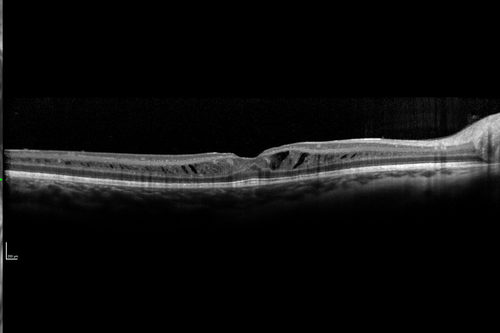

X-linked Juvenille Retinoschisis - Peripheral Retinal Vascular Anomalies - Vitreous Hemorrhage - 8 Year Old Boy

OD: Vertical C/D ratio is 0.2.  There are foveal cysts.  There is also a retinal elevation inferiorly and there are patchy peripheral retinal hemorrhages.

OS: Vertical C/D ratio is 0.2.  There are foveal cysts.  There is peripheral retinal issues with some hemorrhage in some areas of peripheral retinoschisis.